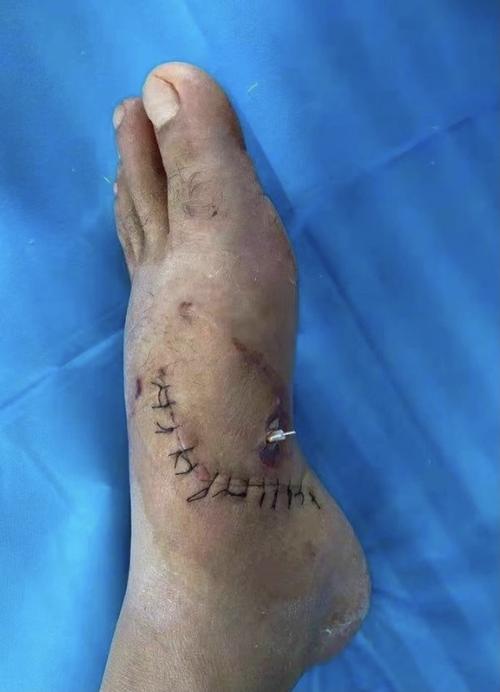

神经吻合 克氏针内固定手术治疗左足内侧电锯割裂伤

术中我们仅用了最简单的材料,仅几枚克氏针就完成了这个复杂的手术.